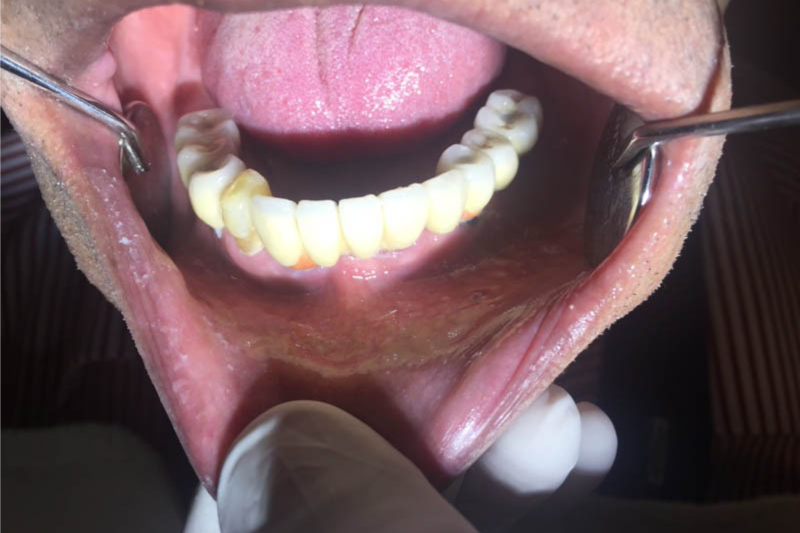

All on 4 All On 6 Implants

All on 4 or all on 6 treatment concepts is a graft less solution that provides patient with a fixed full arched prosthesis on the day of the surgery.

This treatment concept was developed to maximize the use of available remnant bone in atrophic jaws, allowing immediate function and avoiding regenerative procedures that increase the treatment costs and patient morbidity, as well as the complications inherent to these procedures

Advantage – graft less solution, immediate form and function, life changing, scientifically proven, very high success rate